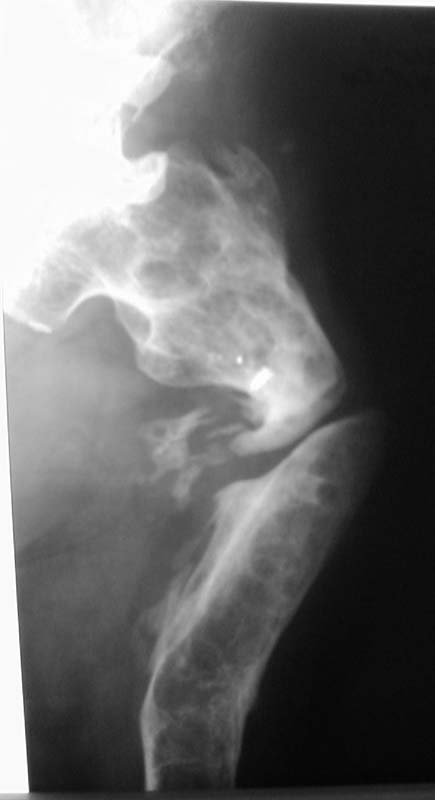

Судя по представленному снимку, есть 3 деформации – Варусная в области ложного сустава - 70°, Вальгусная - 35° в средней трети бедра, и ещё одна вальгусная 8° в области дистального метаэпифиза бедренной кости. Если бы пациент попал ко мне, я сделал бы трилокальный остеосинтез – Открытый погружной копрессионный в области ложного сустава, остеотоми на вершине деформации средней трети бедра для удлинения и коррекции деформации и коррегирующую остеотомию через верхний край мыщелков бедренной кости. Для оппонентов такой тактики сразу оговорюсь, что коррекция анатомической и механической оси при наличии срастающегося ложного сустава критична для профилактики рефрактуры.

Хотя я полагаю, что открытый билокальный остеосинтез тоже может иметь место в данной ситуации, при котором откратый погружной остеосинтез ложного сустава будет сочетаться с остеотомией средней трети бедра для коррекции механической оси (я подчёркиваю механической) бедра. Для этого надо произвести перерасчёты в конце удлинения по снимкам бедра на всю длину.

По поводу операции на ложном суставе: необходимо убрать все фиброзные ткани между концами отломков, вскрыть каналы проксимального и дисталного отломков для улучшения кровообращения в месте сращения, проксимальному отломку придать овальную форму вершиной вверх и погрузить дистальный отломок в проксимальный на пол сантиметра, это необходимо для увеличения площади контакта между отломками. Будьте осторожны с одномоментным устранением деформации! Следите за пульсом на дистальной части ноги. Не забывайте, что аппарат Илизарова позволяет устранить деформацию постепенно, что более физиологично для мягких тканей.

Просится "русский замок" с последующим удлинением на двух уровнях. Нельзя ли посмотреть тазобедренный сустав?